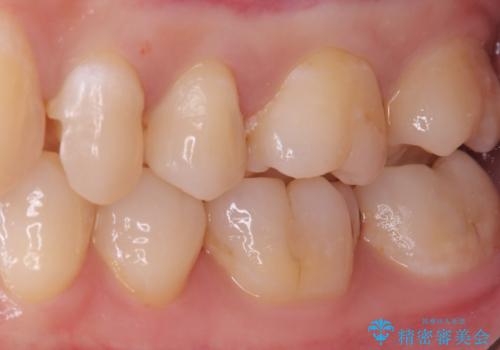

- 主訴:左上真ん中らへんの歯が欠けてしみるので治したい

審美性、適合性の良いセラミックインレーでのやり替えとなりました。

左上4近心に実質欠損を認め、遠心から咬合面にかけてはCR修復が施されていたため、MODインレー窩洞としました。

インレー接着操作時はラバーダム防湿を行っています。